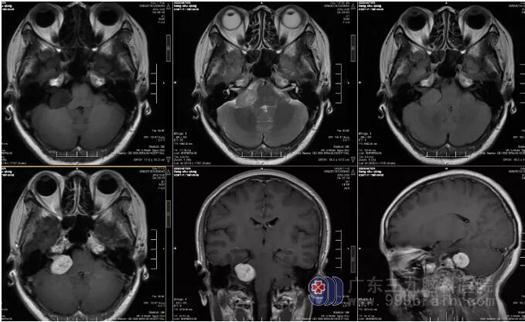

图2:对比PACS图像(2019-9-17MR),现:右侧桥小脑角区示一团片状长T1长T2异常信号影,FLAIR序列呈高信号,范围较前略增大,现大小约25mm×21mm×22mm,增强后病变呈不均匀明显强化,邻近听神经增粗、强化较前明显,邻近脑膜轻度增厚、强化。右侧小脑半于及桥臂轻度受压。